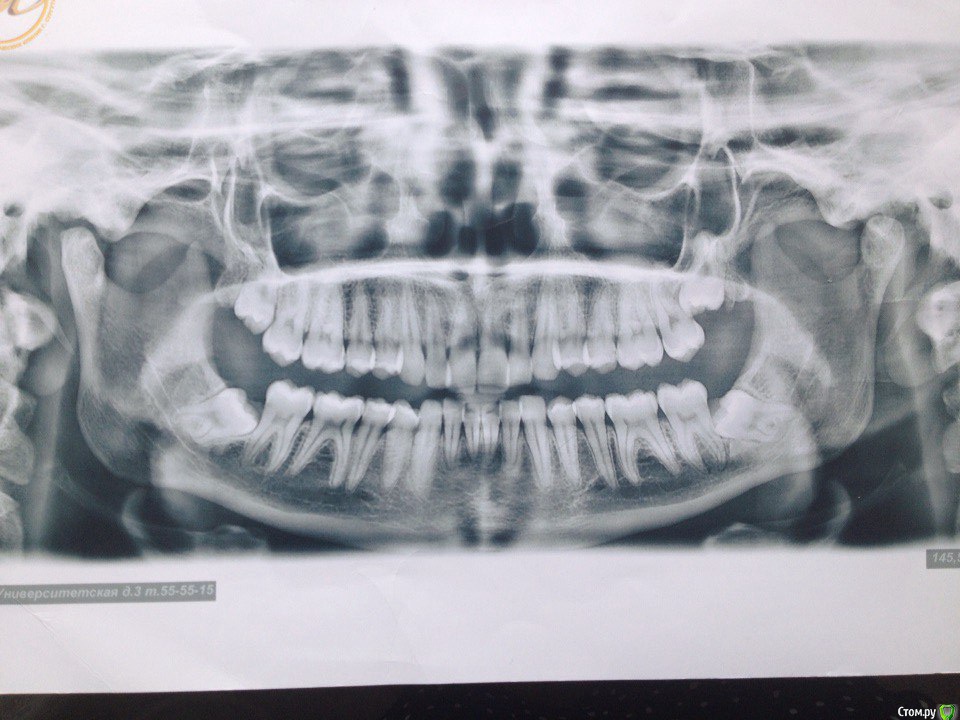

Поставила керамические брекеты в марте 2015 года, ставила для выравнивания зубов (торчали два передних зуба на нижней и на верхней челюсти), проблем с ВНЧС не было, только скрипела во сне зубами, муж неоднократно замечал. На первичной консультации отртодонта предупредила о бруксизме, сказал все нормально, все подобные проблемы именно брекетами и лечатся. Перед установкой делали только ОПТГ и фотографии. Прикус был немного глубокий, как я сама понимаю, во всяком случае от врачей никогда не слышала, что у меня какой-то неправильный прикус. Через месяц после ношения брекетов перестал открываться рот, просто к вечеру я заметила, что не могу его открыть широко, не влазила даже ложка, на осмотре у ортодонта он немножко подпилил накладки, которые были установлены на 6 зубах на НЧ. Ничего не изменилось, на след.осмотре убрал накладки совсем, рот начал открываться, через щелчок или хруст, но не прямо, для широко открытого рта мне приходится делать движение вправо и только так рот открывается до конца, сильных болей не было и нет, бывает ноет в левой стороне возле уха. через несколько месяцев ношения брекетов начала замечать, что челюсть уходит вправо. Вообще на протяжении всего ношения брекетов испытывала дискомфорт в мышцах, все тянуло, и какие то тяжелые челюсти казались. 15 мая сняли брекеты, сделали слепки для капп, мой ортодонт сказал, что сейчас нужно удалять все оставшиеся 8 и походить к остеопату или мануальщику, если не поможет возвращаться делать аксиографию и ставить другие брекеты, на вопрос чем они отличаются он ответил, что с ними можно зуб наклонять в любом положении, в отличии от этих, т.к. с этими брекетами зубы встают только на 90градусов, после снятия брекетов чувствую себя хуже, боль начала появляться в левом ухе, ужасно все напряжено. В нашем городе гнатологов и подобных специалистов нет, ходила на протяжении года к нескольким ортодонтам на консультацию никакой конкретики, грубо говоря все пожимали плечами, не знаю как быть, какие обследования пройти, не поторопились ли мы снимать брекеты (он настаивал), и к кому обратиться, ваше мнение с чем это связано и как теперь решить проблему?